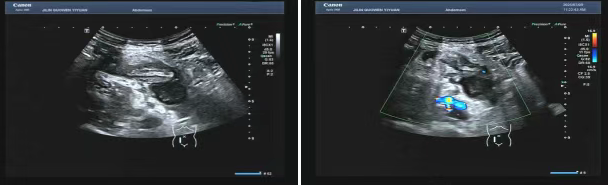

80 歲的張爺爺(化名)因前列腺增生前往國文醫(yī)院就診,泌尿外科為其開具了泌尿系超聲檢查。超聲科醫(yī)生在檢查過程中,憑借敏銳的觀察力,發(fā)現(xiàn)患者右下腹有異?;旌匣芈暟鼔K。醫(yī)生沒有放過這一異常,立即展開進一步探查,結果顯示包塊內(nèi)疑似有闌尾結構,且周圍組織存在粘連,還伴有液性暗區(qū)??紤]到老年患者病情往往較為隱匿,癥狀也不典型,醫(yī)生第一時間與臨床醫(yī)生溝通,建議進行緊急處理。隨后,經(jīng)過臨床醫(yī)生詳細檢查,患者迅速辦理住院并接受手術,術后病理檢查結果確診為 “闌尾壞疽伴穿孔合并膿腫形成”。

主治醫(yī)生介紹,老年人患闌尾炎時,癥狀常常不典型,很容易被誤診為腸胃炎或其他疾病。張爺爺僅表現(xiàn)出輕微腹脹的癥狀。倘若不是超聲檢查時意外發(fā)現(xiàn),極有可能延誤治療,進而引發(fā)感染性休克,甚至危及生命。超聲檢查在這類急腹癥的篩查中,發(fā)揮了至關重要的作用。